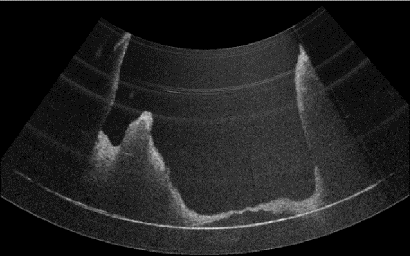

Purpose: Middle ear infection is the most prevalent inflammatory disease, especially among the pediatric population. Current diagnostic methods are subjective and depend on visual cues from an otoscope, which is limited for otologists to identify pathology. To address this shortcoming, endoscopic optical coherence tomography (OCT) provides both morphological and functional in-vivo measurements of the middle ear. However, due to the shadow of prior structures, interpretation of OCT images is challenging and time-consuming. To facilitate fast diagnosis and measurement, improvement in the readability of OCT data is achieved by merging morphological knowledge from ex-vivo middle ear models with OCT volumetric data, so that OCT applications can be further promoted in daily clinical settings. Methods: We propose C2P-Net: a two-staged non-rigid registration pipeline for complete to partial point clouds, which are sampled from ex-vivo and in-vivo OCT models, respectively. To overcome the lack of labeled training data, a fast and effective generation pipeline in Blender3D is designed to simulate middle ear shapes and extract in-vivo noisy and partial point clouds. Results: We evaluate the performance of C2P-Net through experiments on both synthetic and real OCT datasets. The results demonstrate that C2P-Net is generalized to unseen middle ear point clouds and capable of handling realistic noise and incompleteness in synthetic and real OCT data. Conclusion: In this work, we aim to enable diagnosis of middle ear structures with the assistance of OCT images. We propose C2P-Net: a two-staged non-rigid registration pipeline for point clouds to support the interpretation of in-vivo noisy and partial OCT images for the first time. Code is available at: https://gitlab.com/nct\_tso\_public/c2p-net.